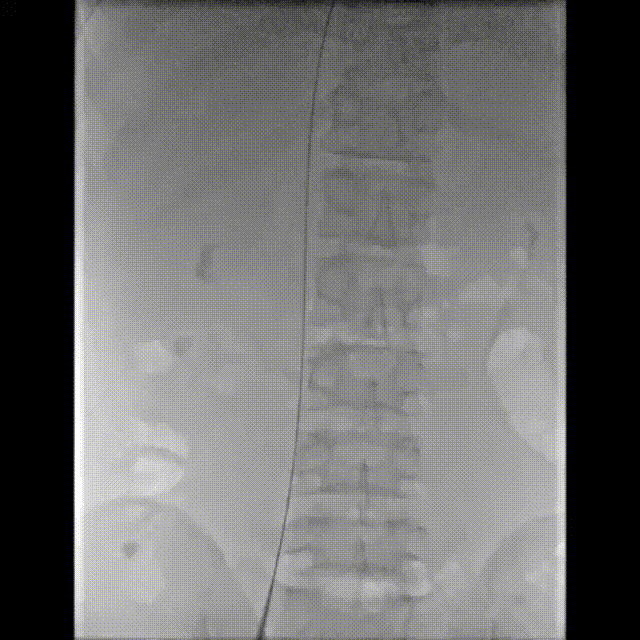

术前造影可见三尖瓣反流

DSA及食道超声引导新型预弯鞘送至三尖瓣